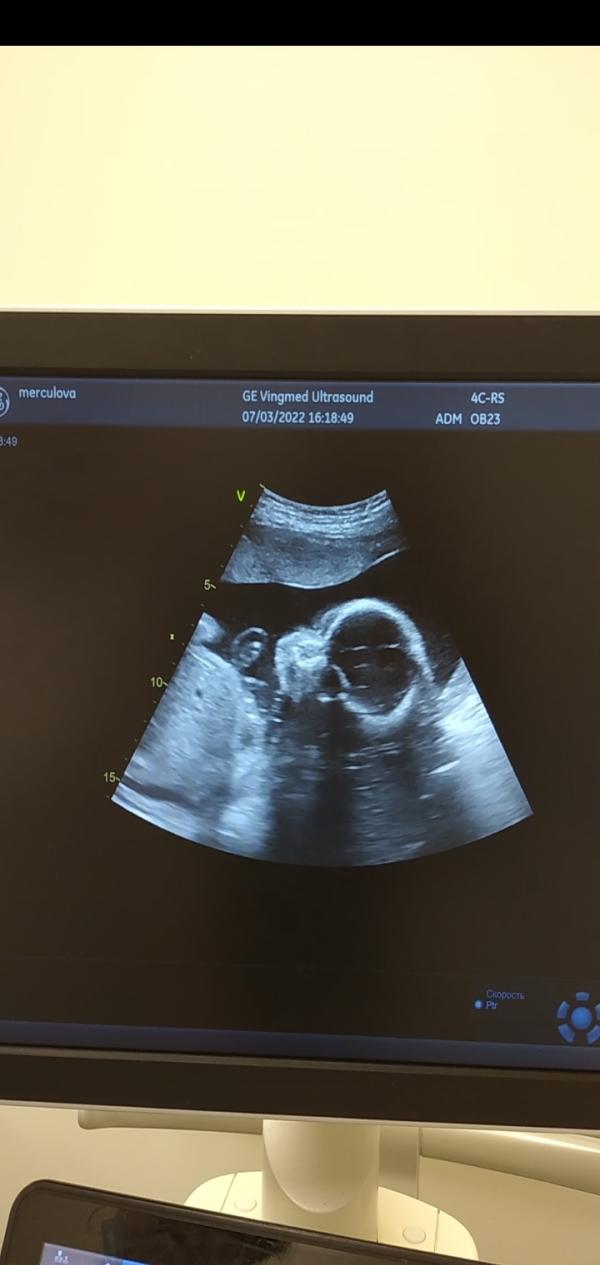

УЗИ 07.03.22: Наша малышка 764гр, активная девчушка, шейка 3,3, полип не нашли, срок 24-25 недель?

Сегодня была на узи! Наша крошка почти 800гр. (764) активная, щекастенькая, девчушка☺️🧡

Делали по животу, полип не увидели (может он вышел?!🙏) шейка 3,3 всё в порядке, чуть меньше по сроку, написали 24-25